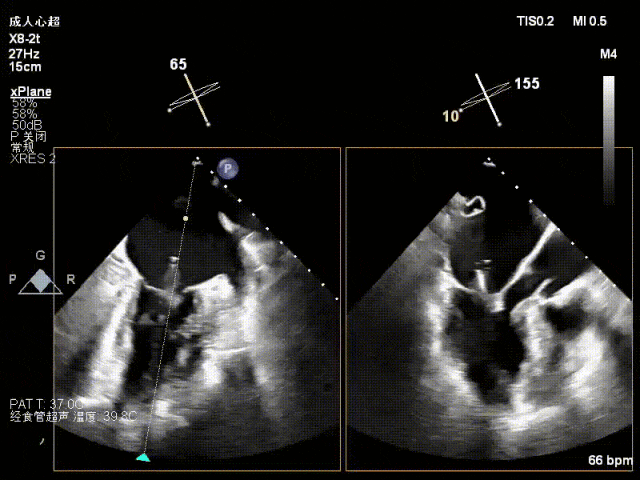

术中超声(关键步骤)

混合性MR,P2脱垂连枷(脱垂范围15mm,连枷间距4mm),腱索断裂

新分型:ACA型,反流2区及两侧,MR 4+,VC:3×14mm

A2:24mm,P2:17mm,AP:38mm,MVA约5.7cm²